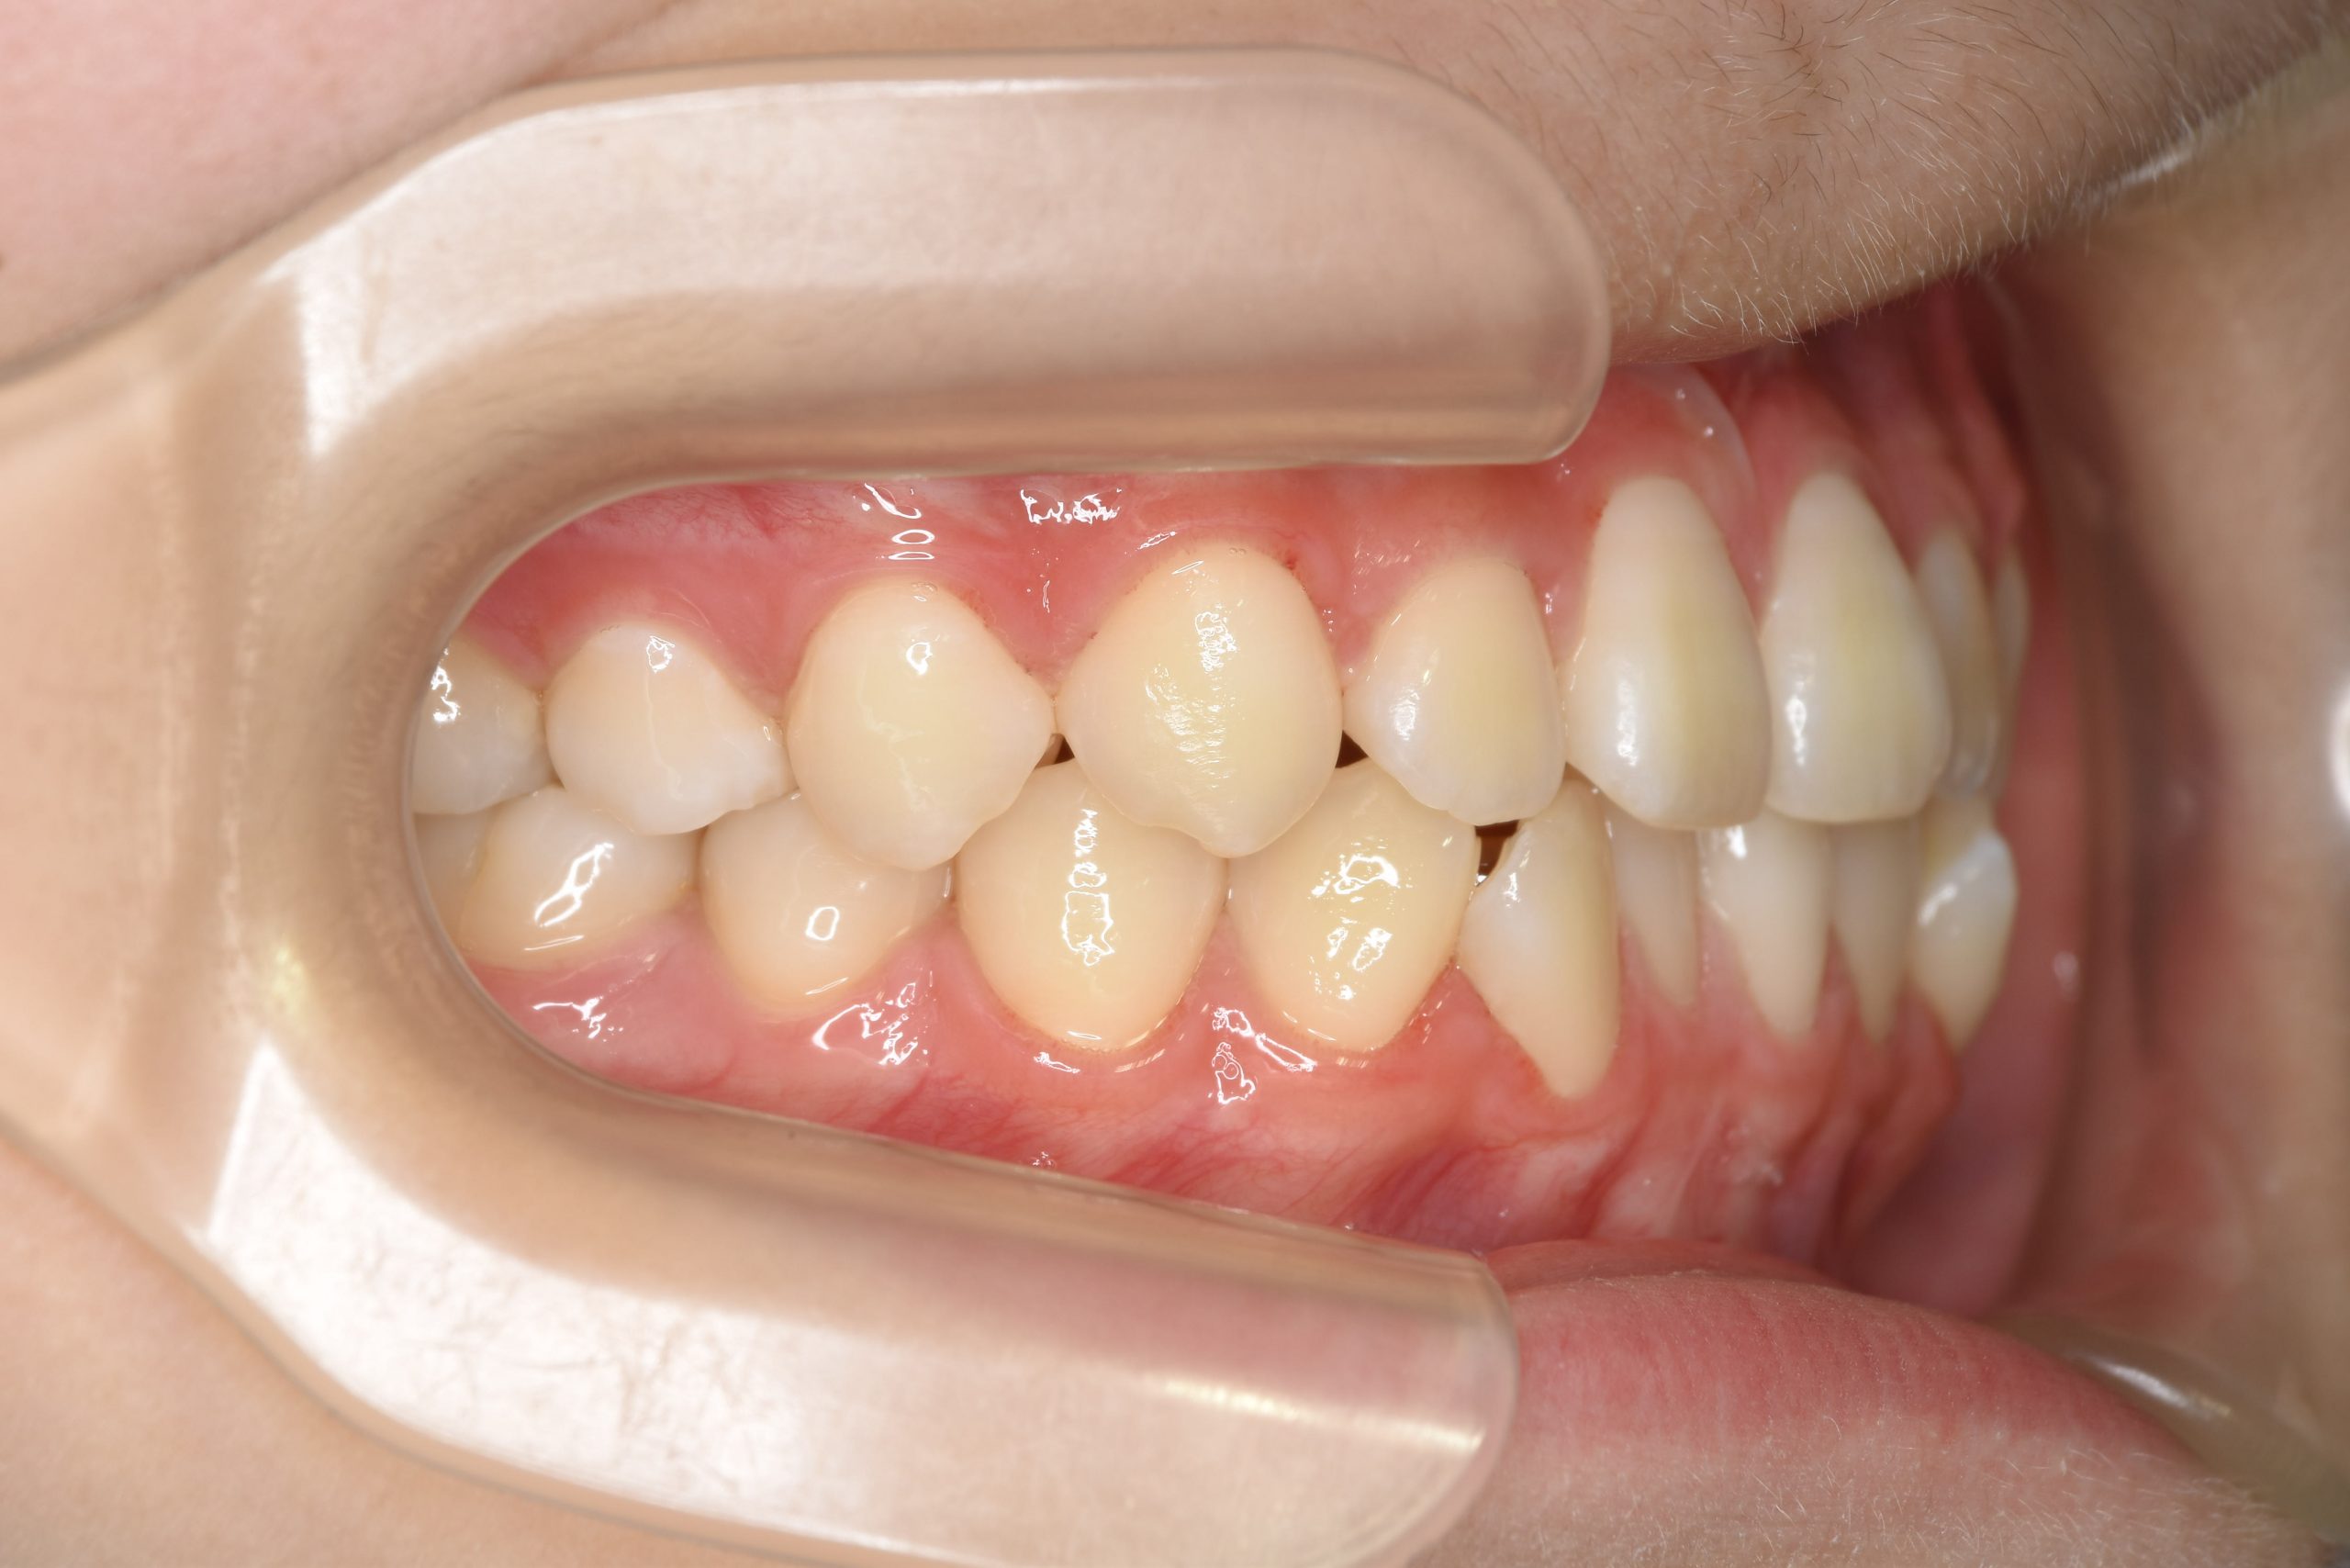

アフター

主訴 受け口

施術内容 上顎急速拡大装置と下顎リンガルアーチを用いて上下顎骨を拡大した。

上顎前方牽引装置を用いて上顎骨を前方に成長促進させた。

その後マウスピース型矯正装置で歯牙を配列し良好な咬合を獲得した。

治癒期間 2年9ヶ月間